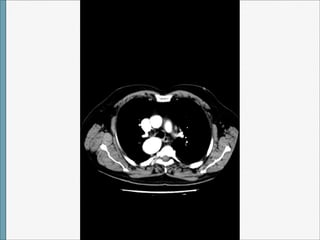

TAC

Arco Aórtico Derecho

1)CON ARTERIA SUBCLAVIA IZQUIERDA ABERRANTE